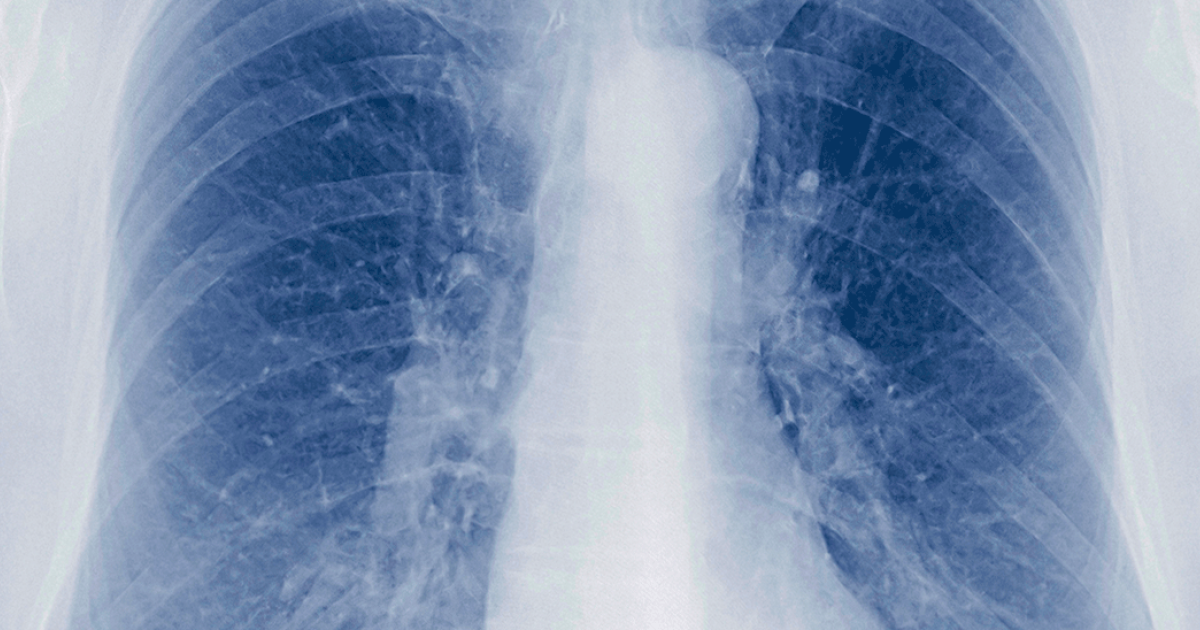

A bronquite é a inflamação dos brônquios, os tubos que levam ar aos seus pulmões. Sabe quando a gente tosse muito, sente o peito apertado e às vezes até sai catarro? Isso pode ser bronquite. Ela pode ser aguda, durando poucas semanas, ou crônica, persistindo por meses ou anos. A forma crônica está ligada a fatores como o cigarro, o que prejudica a função pulmonar e a qualidade de vida.

Identificar a bronquite cedo faz toda a diferença no tratamento. Quando inflama, a passagem de ar fica mais difícil, e o corpo reage com tosse para tentar limpar as vias aéreas. Se você sente esses sintomas com frequência, é essencial procurar um médico. Ele vai te orientar sobre a melhor forma de cuidar da sua saúde respiratória e evitar complicações.